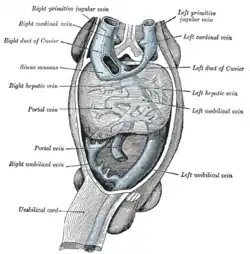

Posterior abdominal wall, after removal of the peritoneum, showing kidneys, suprarenal capsules, and great vessels. (Hepatic veins labeled at center top.) Human embryo with heart and anterior body-wall removed to show the sinus venosus and its tributaries.

Human embryo with heart and anterior body-wall removed to show the sinus venosus and its tributaries. Longitudinal section of a hepatic vein.